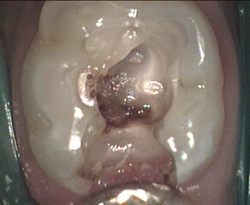

Hidden very large cavity Red decay finder

very deep now protective base material added

Final filling